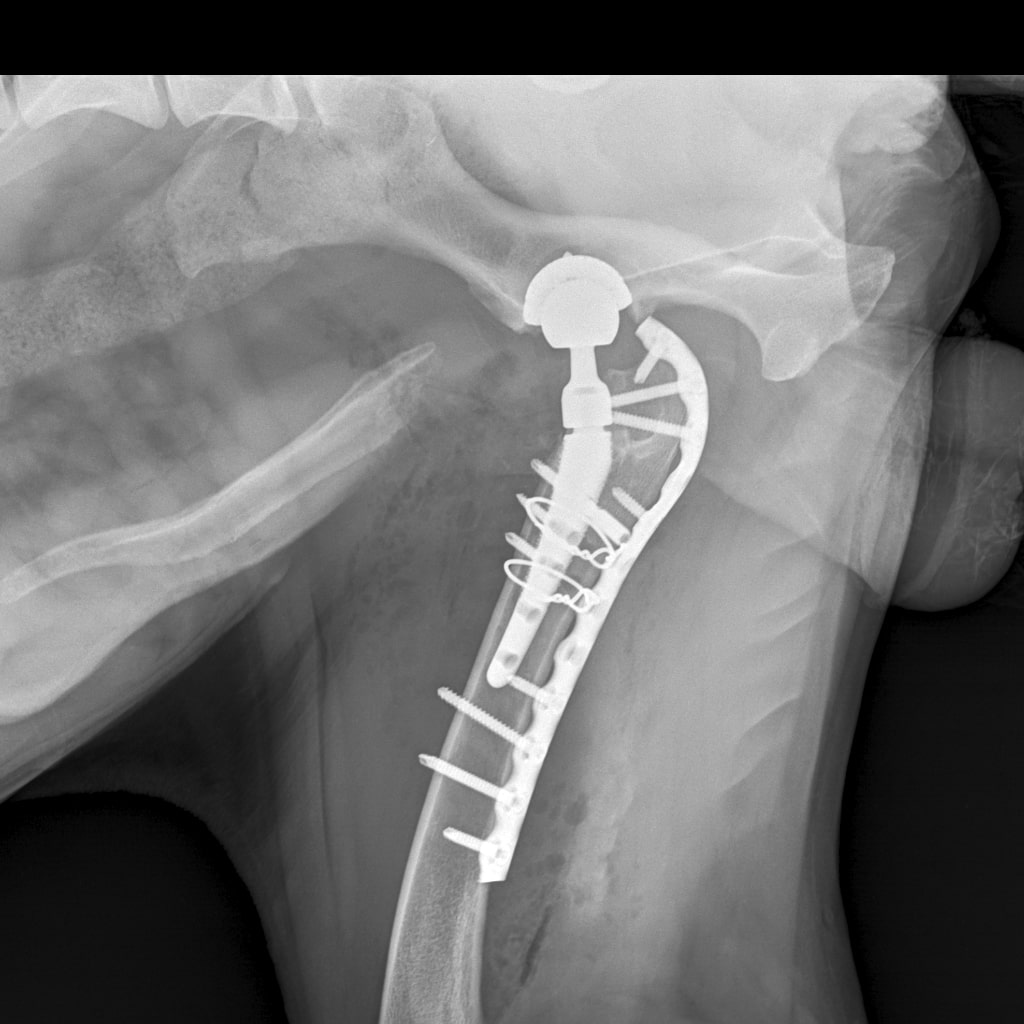

26 августа к 10 утра голодными, нас ждут на контрольный рентген в клинике на Вернадского.

Рентген будет под седацией

За время противовоспалительной терапии снизилось воспаление и в левом тазобедренном суставе, но увы, форма головки бедренной кости и состояние шейки бедра , лучше не стали:(((

Операция однозначно нужна.

Снимки столь качественные, что их можно в учебник

Перевели все собранные на Бруно деньги на счет клиники.

Готовимся ко второй операции 3 октября

Железный дровосек